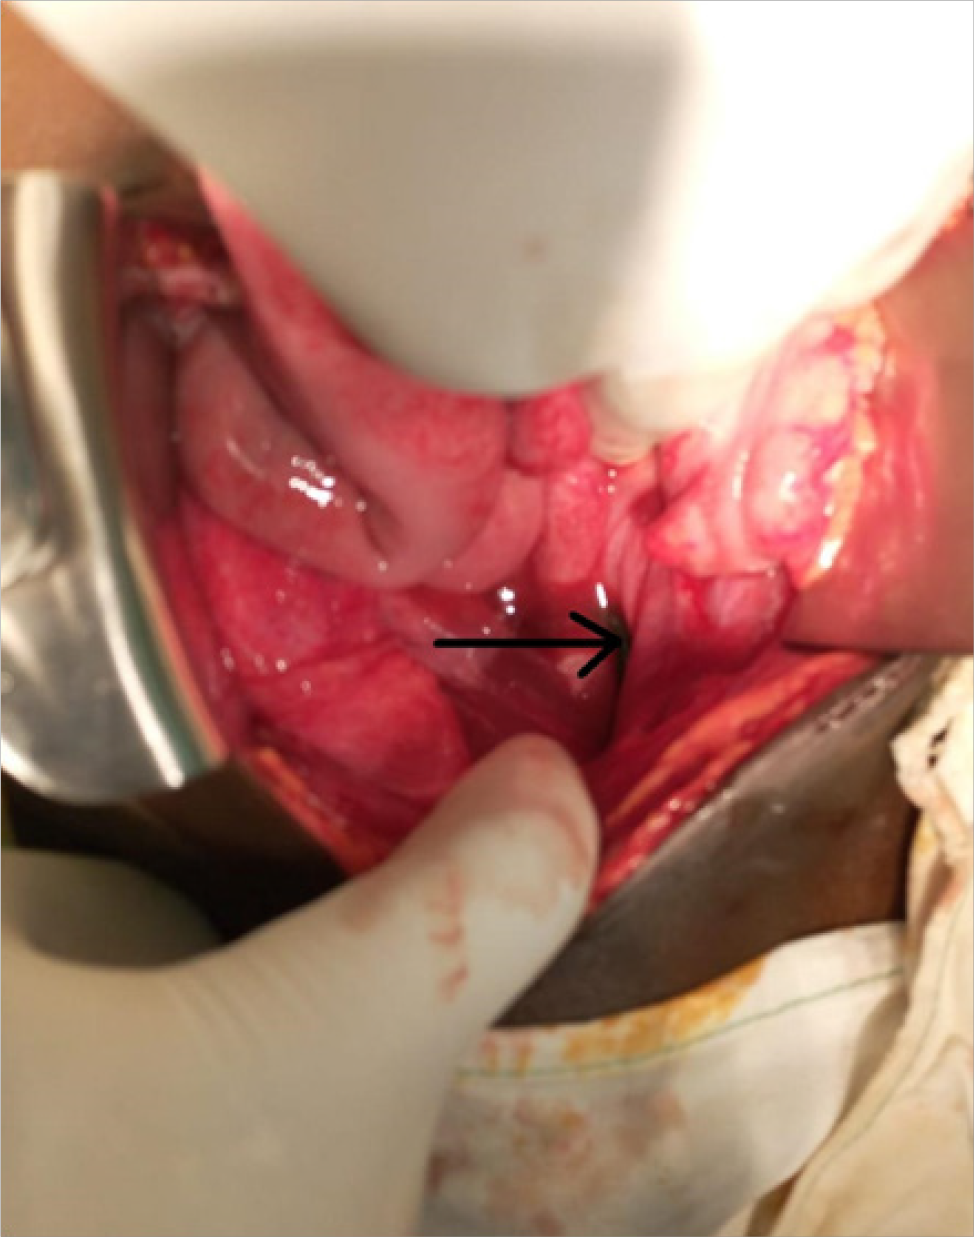

We present a case of an eleven-year old school boy slid and fell on an iron rod that penetrated his rectum through his anal canal. Presented with clinical features of peritonitis, where emergency laparotomy was done and the iron rod was extracted abdominally with primary repair of the rectum. The boy recovered well and was discharged four days after with no complications.